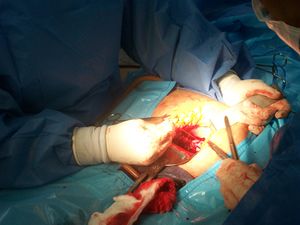

تستغرق الولادة القيصرية من 45 دقيقة إلى ساعة.[2] يمكن إجراؤها باستخدام التخدير النخاعي، حيث تكون المرأة مستيقظة، أو تحت التخدير العام.[2] تستخدم القسطرة البولية لتصريف المثانة، ثم يُنظف جلد البطن باستخدام مطهر.[2] عادة ما يُجرى شق بطول 15 سم تقريباً أسفل بطن الأم. [2] ثم يُفتح الرحم بشق ثانٍ ثم يُولد الطفل.[2] ثم تُغلق الشقوق بالمخيط.[2] عادة يمكن للمرأة البدء في إرضاع وليدها بمجرد خروجها من غرفة العمليات والإفاقة.[5] في كثير من الأحيان، يلزم قضاء عدة أيام في المستشفى للتعافي بشكل كافٍ قبل العودة إلى المنزل.[2]

تستخدم الوقاية المضادة للميكروبات قبل الشق.[70] يُشق الرحم، ويُمدد هذا الشق بضغط غير حاد على طول محور الرأس والذيل.[70] يولد الطفل ثم تزال المشيمة.[70] ثم يتخذ الجراح قرارًا بشأن جعل exteriorization الرحم.[70] يستخدم إغلاق الرحم أحادي الطبقة عندما لا ترغب الأم في الحمل مستقبلاً.[70] عندما يبلغ سمك النسيج تحت الجلد 2 سم أو أكثر، يقوم الجراح بخياطة الشق.[70] تشمل الممارسات غير المرغوبة تمدد عنق الرحم، تصريف أي سوائل تحت الجلد،[71] أو العلاج بالأكسجين التكميلي للوقاية من حدوث العدوى.[70]